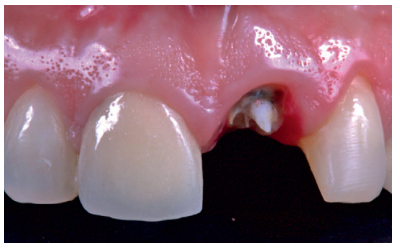

This describes the clinical case of a 52-year-old woman who came to the dentist surgery due to de-cementation of a tooth-supported metal-ceramic crown on tooth 2.1 (ICSI), see Figures 1-3. The patient reported it as of high concern for her aesthetically.

Examination

The patient reported pain when chewing in the anterosuperior sector, located in the ICSI area, which disappeared after taking painkillers. An intraoral clinical examination revealed that the decemented crown retained remains of the ICSI stump, as well as a cast post that served as a scaffold for the restoration. The ICSI was a root remnant, with total loss of tooth structure and no ferrule that might ensure a new rehabilitation9 . The patient had a medium smile line and a fine gingival phenotype, which was accompanied by gingival recession in the affected tooth, as well as in the contiguous teeth of the second quadrant. She presented palpation, percussion and a positive bite test and negative vitality in the ICSI, with no periodontal pocket (probe depth < 3 mm) or mobility. An additional radiological examination was carried out, which included a periapical radiograph and cone beam computed tomography (CBCT), see Figure 4. After evaluating these tests, a subgingival complete horizontal coronary fracture without periapical bone involvement was observed.